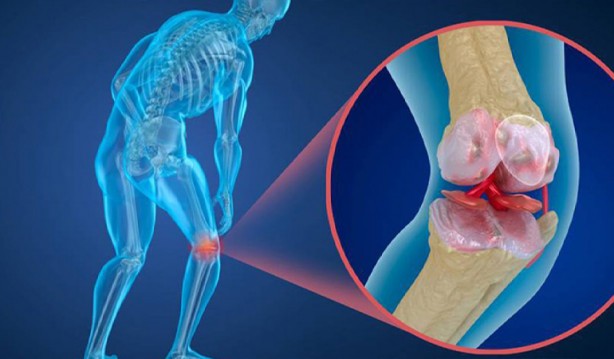

Ayrıca romatizma tedavisinde kullanılan kortizonlu ilaçlar, epilepsi ilaçları, kanser ilaçları, bazı mide ilaçları kullanmak, romatiod artrit, kanser, lupus, multipe myleom, böbrek karaciğer hastalıkları gibi hastalıklar geçirmek, hareketsiz bir yaşama sahip olmak, sigara kullanmak, sık alkol kullanmak, besinlerle yeterince kalsiyum almamak, aşırı miktarda tiroit hormonu kullanmak, aşırı zayıf olmak, gereğinden daha az beslenmek ve zayıflama ameliyatı olmak da kemik erimesine neden olabilir.

Kemik erimesi omurlarda, el bileğinde ve kalça kemiğinde kırılmalara yol açarak sakatlıklara hatta ölümlere yol açabilir” şeklinde konuştu.